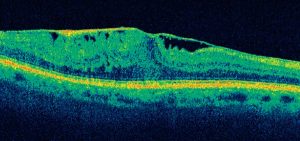

La tomografia a coerenza ottica (OCT) è un test di imaging non invasivo che utilizza le onde di luce per scattare foto della retina, e in particolare della macula. La macula è una parte della retina deputata alla visione a colori e ad alta definizione.

Con l’OCT possono essere analizzati e mappati tutti gli strati retinici, inoltre è possibile rilevare lo spessore retinico. Questi dati aiutano a effettuare una corretta diagnosi e a fornire delle indicazioni per il trattamento del glaucoma e delle patologie retiniche, malattie come la degenerazione maculare senile e la retinopatia diabetica.

Se in atto è presente o è stata presente una di queste condizioni retiniche è importante eseguire l’OCT.